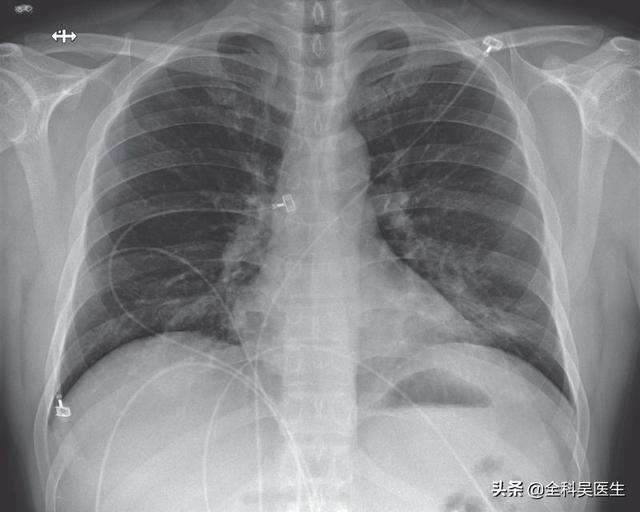

胸部レントゲン写真や肺のCT画像では、肺の外側の帯状に認められる斑状の影や、重症例では肺の固い影が認められることがある。

2.肺炎の画像的特徴を有する:肺に炎症性変化があることを意味し、肺の外側の帯状に明らかな複数の小さな斑状影や間質性変化、さらには両肺に複数の地中影や浸潤影などの変化を示します。ウイルスが肺に侵入した後、肺にうっ血や水腫が生じ、X線やCTで高密度の影が観察されるからです。

②胸部CTを撮影すると、初期には多発性の斑状陰影や間質性変化を示唆することがあり、肺外帯に明らかで、その後の検討で両肺に多発性の地中影や浸潤影が生じ、重症例では固形肺病変が出現する。

②.肺炎の画像的特徴が胸部に認められる。

初期には複数の小さな斑状影と間質性変化を呈し、両肺に多発する地硝子影や浸潤影へと進行し、重症例では肺に固形変化が生じ、一般に「白い肺」と呼ばれる状態になることもある。